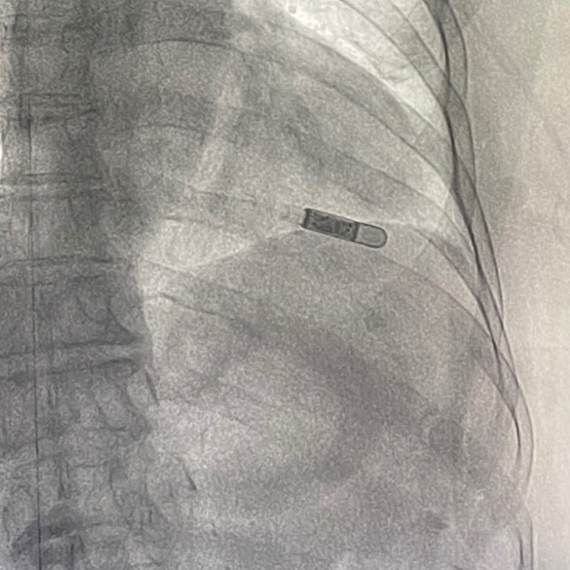

根据患者发病特点,福建医科大学附属泉州市第一医院心内科心律失常诊疗团队决定为其植入最新的ICM以捕捉隐匿性心律失常事件。

ICM是一款“微创”植入的心律失常事件监测器,可持续监测3年,并自动发现各种心跳异常,如停搏,心跳过缓、过速,房颤等!是临床医生评估潜在心律失常的理想方法,其诊断率为常规院内心电图监测的 6.5 倍¹,可以帮助 78%的患者明确诊断²。

Reveal LINQ比上一代Reveal XT,体积缩小87%,假阳性率降低54%,房颤识别率97.8%。真正实现了微创、智能化的“芯片”式监测系统!

手术仅十分钟,“芯片”就成功植入